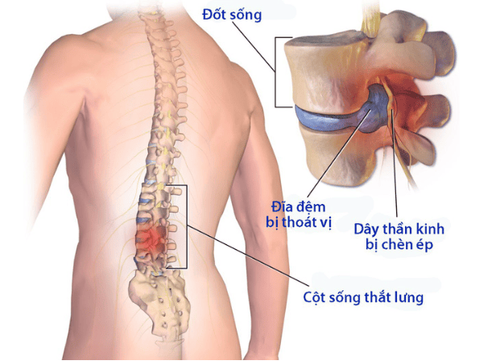

Chấn thương đầu xảy ra do chấn thương da đầu, hộp sọ hoặc não. Vết thương ở đầu được phân loại là kín, không có vết cắt hoặc vết rách trên da, hoặc xuyên thủng, trong đó da hoặc xương hộp sọ bị vỡ. Chấn thương sọ não có nhiều mức độ từ nhẹ (gọi là chấn thương sọ não nhẹ) đến nặng.

Các triệu chứng của chấn thương đầu có thể xảy ra ngay sau chấn thương, hoặc chúng có thể phát triển chậm trong vài giờ hoặc vài ngày. Các loại và triệu chứng cụ thể của chấn thương đầu bao gồm:

Điều này bao gồm chấn thương não do một cú đánh vào đầu hoặc cơ thể, ngã hoặc một chấn thương khác làm chùn hoặc rung não bên trong hộp sọ. Những người bị chấn động có thể không phải lúc nào cũng biểu hiện các triệu chứng rõ ràng cho người khác. Các triệu chứng của chấn động và chấn thương sọ não nhẹ bao gồm:

2.2 Chảy máu

Một vết bầm tím của mô não thường kết hợp với sưng (phù nề) và tăng áp lực trong hộp sọ, được gọi là áp lực nội sọ (ICP). Các triệu chứng của tăng áp lực trong não và hộp sọ bao gồm: đồng tử giãn ra, huyết áp cao, nhịp tim thấp và nhịp thở bất thường.

2.3 Gãy xương

Một vết nứt hoặc vỡ trong hộp sọ, có hoặc không có vết rách trên da. Các triệu chứng của gãy xương sọ bao gồm: Sưng tấy, biến dạng hộp sọ, bầm tím quanh mắt hoặc sau tai, chất lỏng trong suốt rỉ ra từ mũi hoặc tai.

2.4 Chấn thương cắt (còn gọi là chấn thương trục lan tỏa)

Loại chấn thương này xảy ra khi não bị va đập mạnh vào bên trong hộp sọ. Các sợi thần kinh kéo dài từ trung tâm của tế bào thần kinh bị kéo căng hoặc rách, làm tổn thương vĩnh viễn các tế bào não và gây ra các biến chứng khác trong hệ thần kinh. Triệu chứng chính của chấn thương cắt là mất ý thức kéo dài.